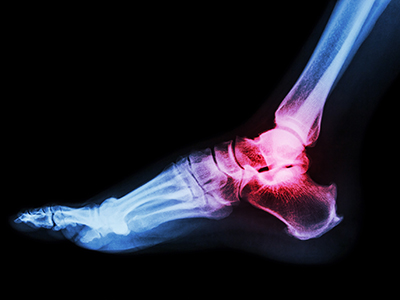

Does COVID-19 affect times to surgery and lengths of stay for patients with ankle fractures?

A group of faculty and trainees recently set out to answer that question and published “Ankle Fracture and Length of Stay in US Adult Population Using Data From the National COVID Cohort Collaborative” in the Foot & Ankle Orthopaedics journal.

Ultimately, of 4,735 adults with ankle fracture surgery, the COVID-19–positive group had significantly longer times to and longer lengths of stay compared to the COVID-19–negative group.